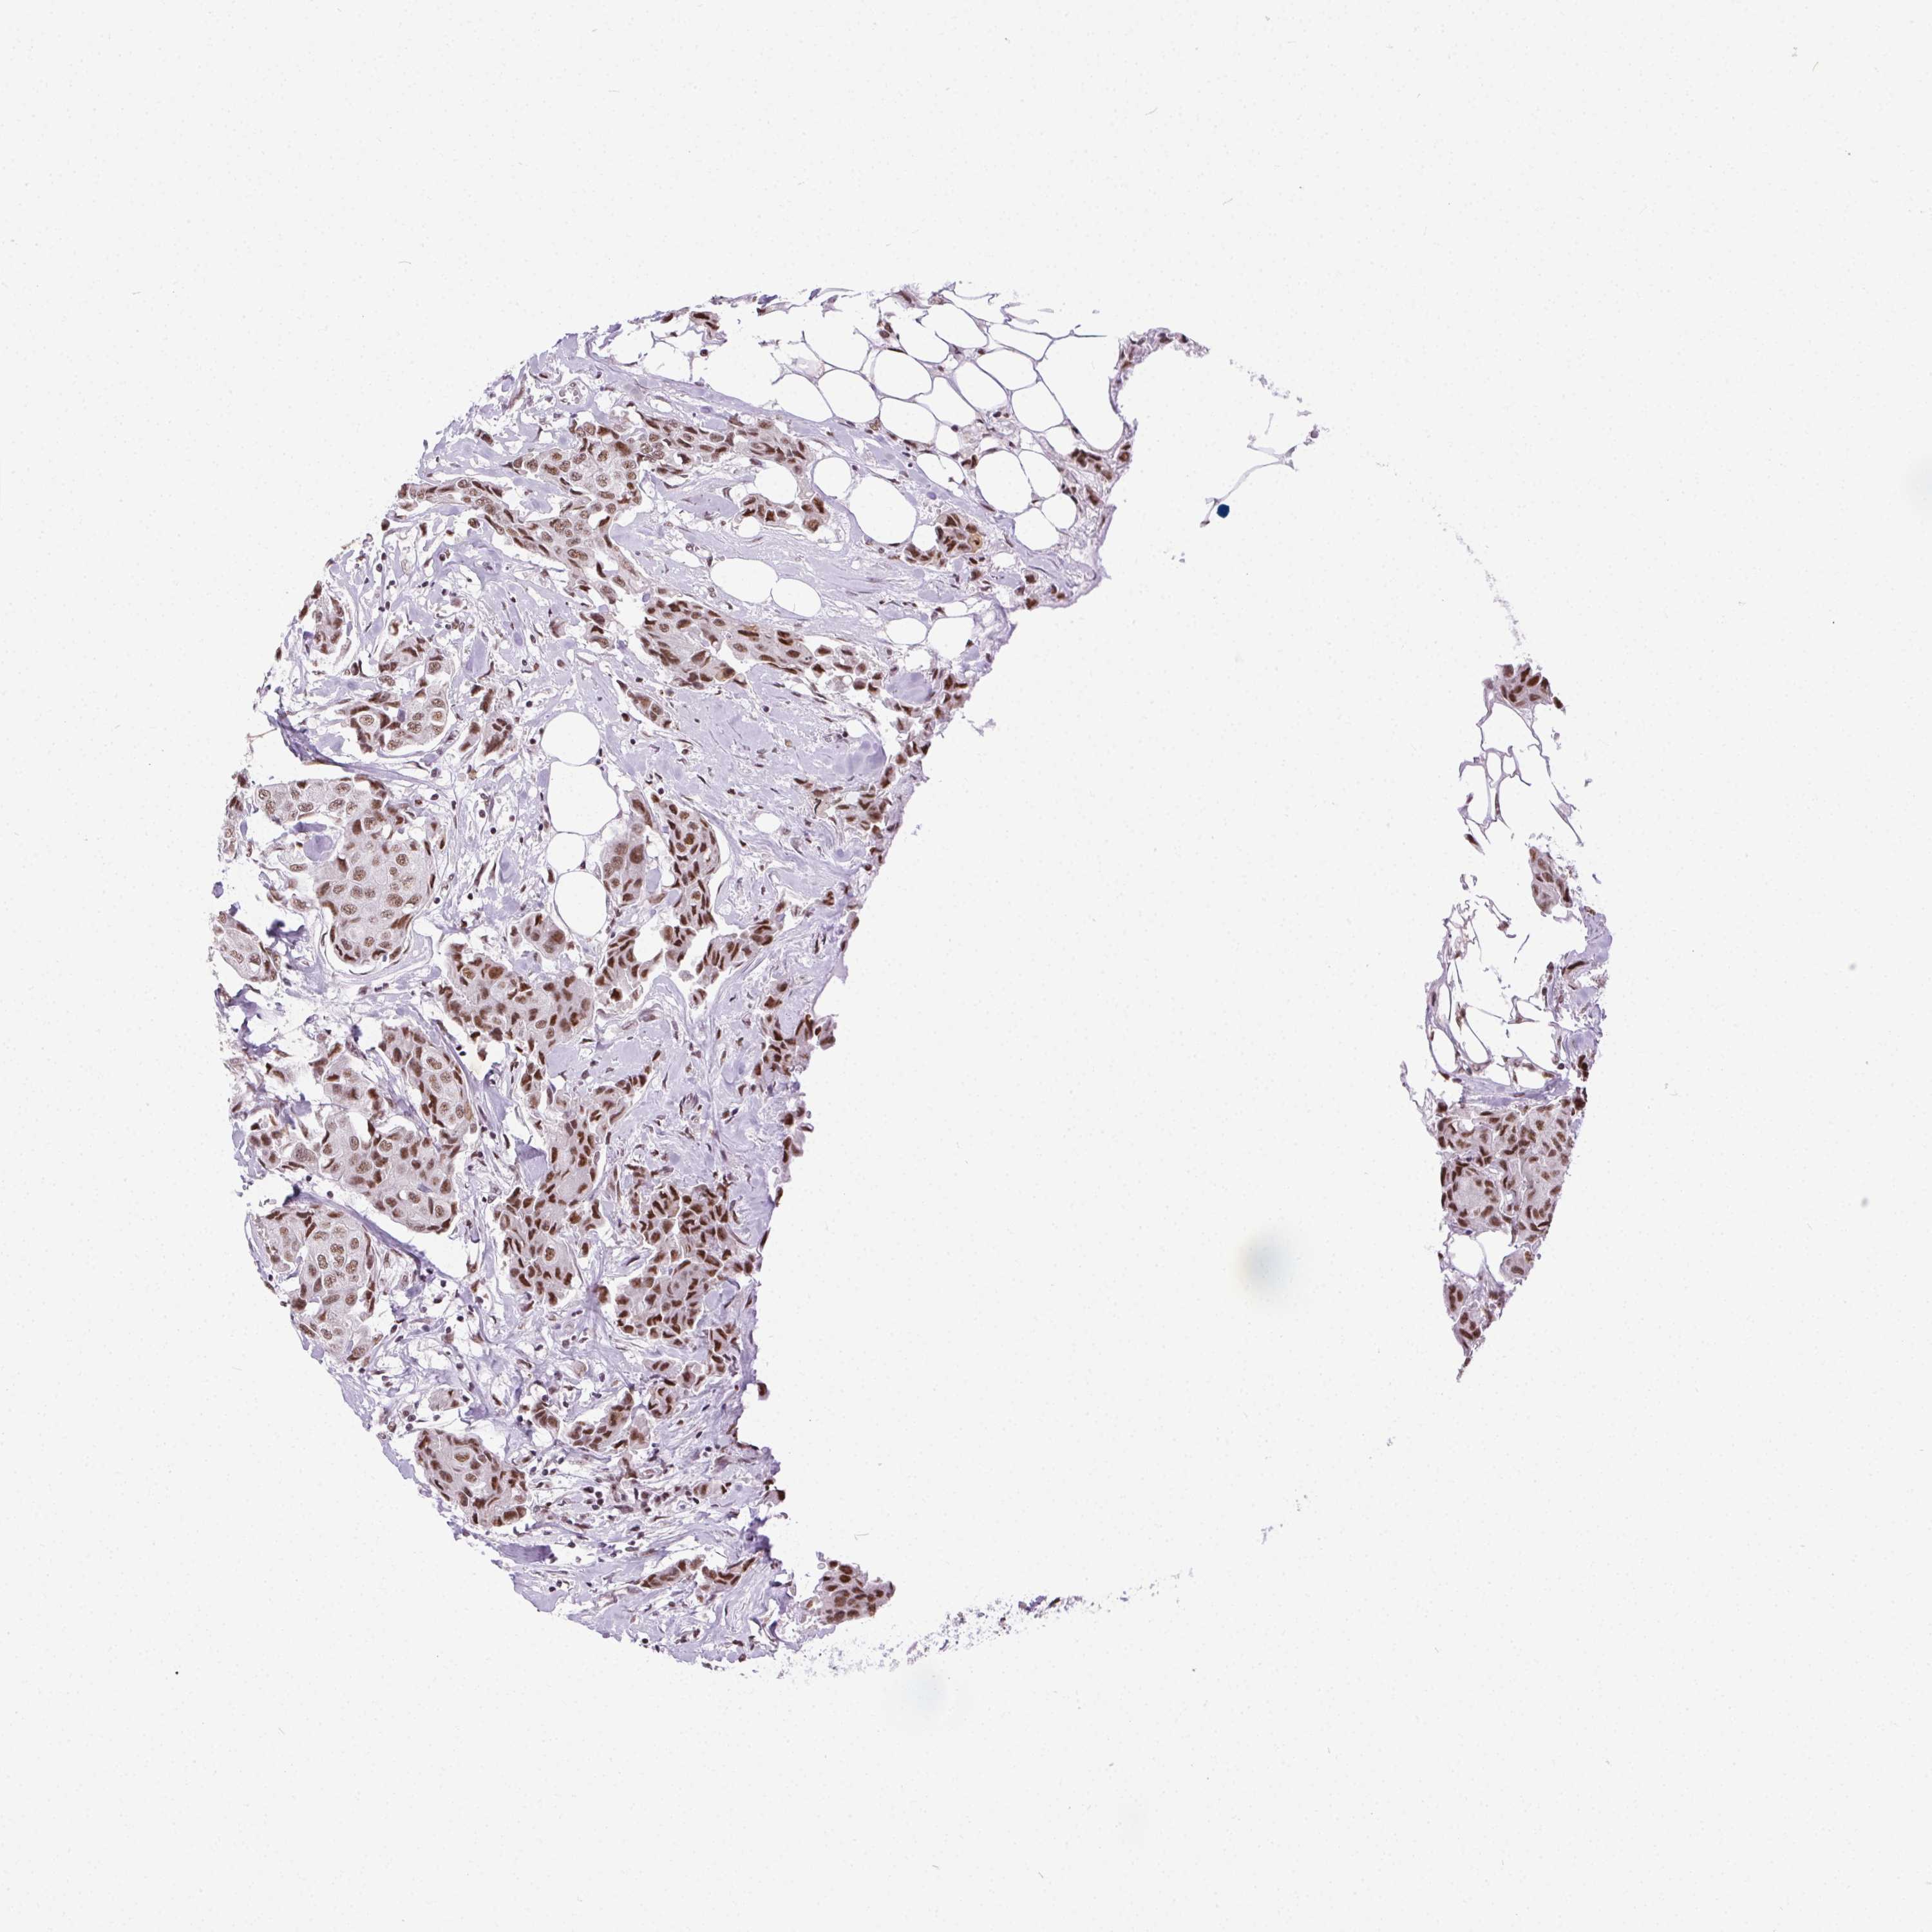

CANCER BREAST CANCER Show tissue menu

BRCA TCGA BRCA VALIDATION PROTEIN EXPRESSION